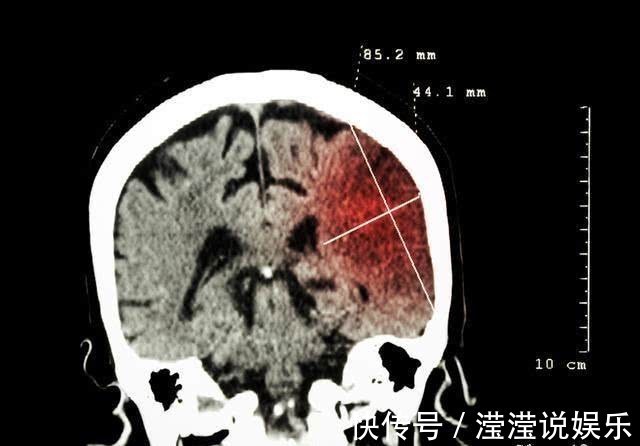

43岁的罗先生早上起床上厕所时,突然发现自己讲话困难,身体的右侧无法移动,他只能活动左侧身体,还没能给妻子求救信号,就昏了过去。妻子看到时,立即拨打120救护车,这时已经过去很久了。医生到达后,初步诊断是脑血管疾病。当到达医院后,检查了脑CT,果然如医生所言,诊断结果为急性脑梗塞!

医生立即进行了静脉溶栓治疗,但由于罗先生脑血管堵塞严重,耽搁时间过长。抢救过程中很惊险,家属随即接到病危通知书。溶栓治疗后约2小时,罗先生病情得到缓解,意识逐渐觉醒,四肢肌力也在慢慢恢复。病情好转后,就被转到住院部。在此期间,对罗先生进行了脑血管造影,发现罗先生在脑血管已严重狭窄。幸好及时送到医院,否则很可能危及生命。